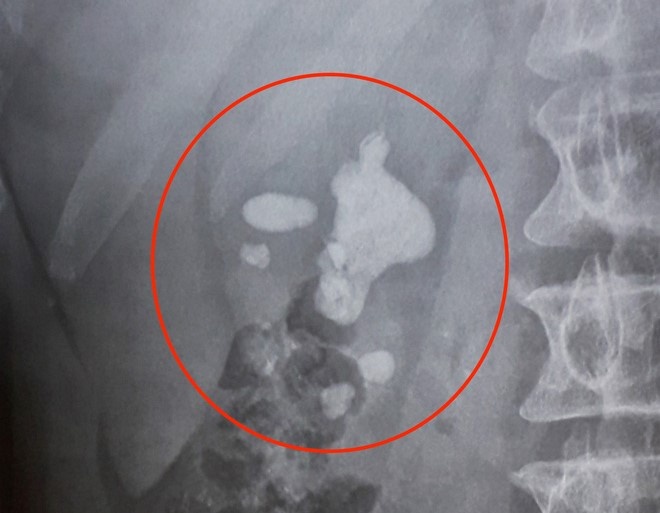

Hình ảnh chụp X-quang cho thấy viên sỏi có kích thước rất lớn trong thận nam bệnh nhân.

Qua chụp CT và siêu âm, các bác sĩ phát hiện trong thận ông H. có một viên sỏi rất lớn dạng tảng san hô đã chiếm thận phải bệnh nhân.

Các bác sĩ phát hiện bệnh nhân có viên sỏi lớn dạng tảng san hô chiếm hầu hết thận phải.